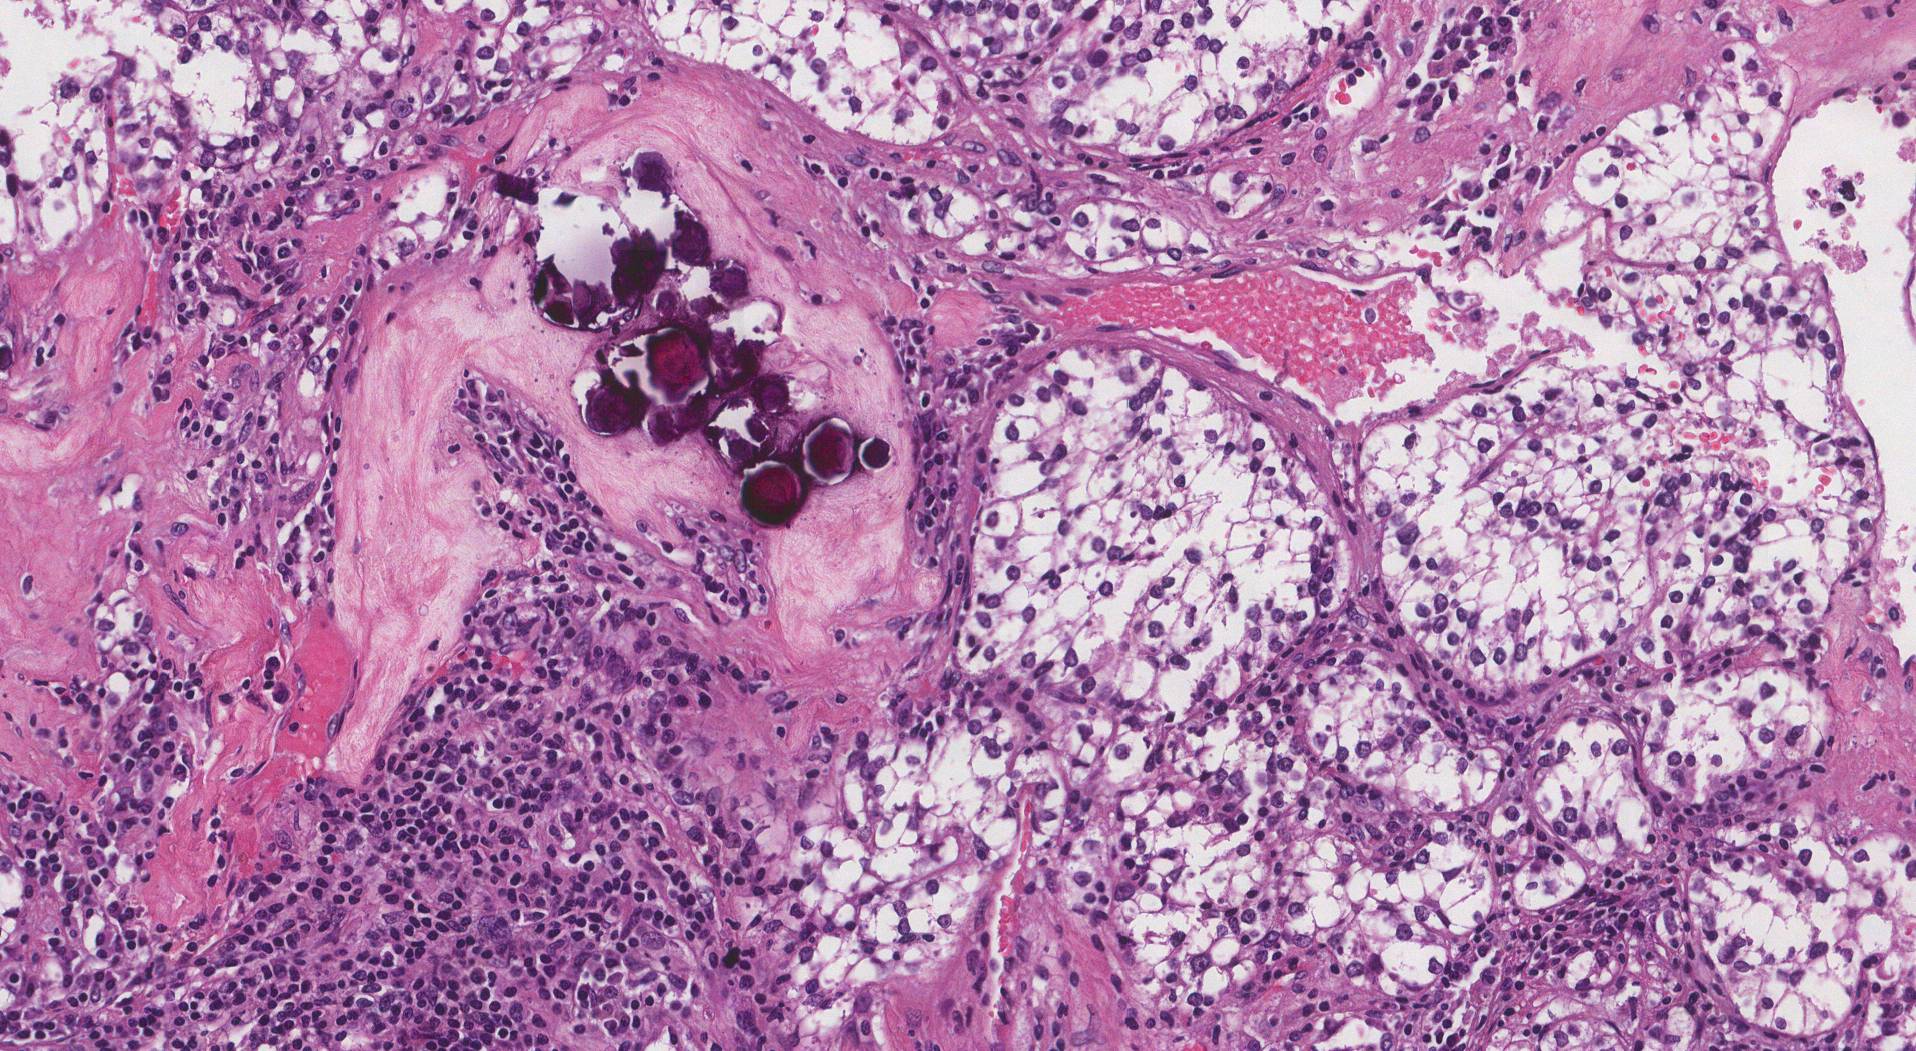

腎細胞癌 (RCC) は最も一般的な種類の腎臓癌であり、

腎細胞がんはどのように診断されますか?

医師は血液検査、尿検査、画像検査を経て腎細胞がんを診断できます。他の種類のがんとは異なり、生検は